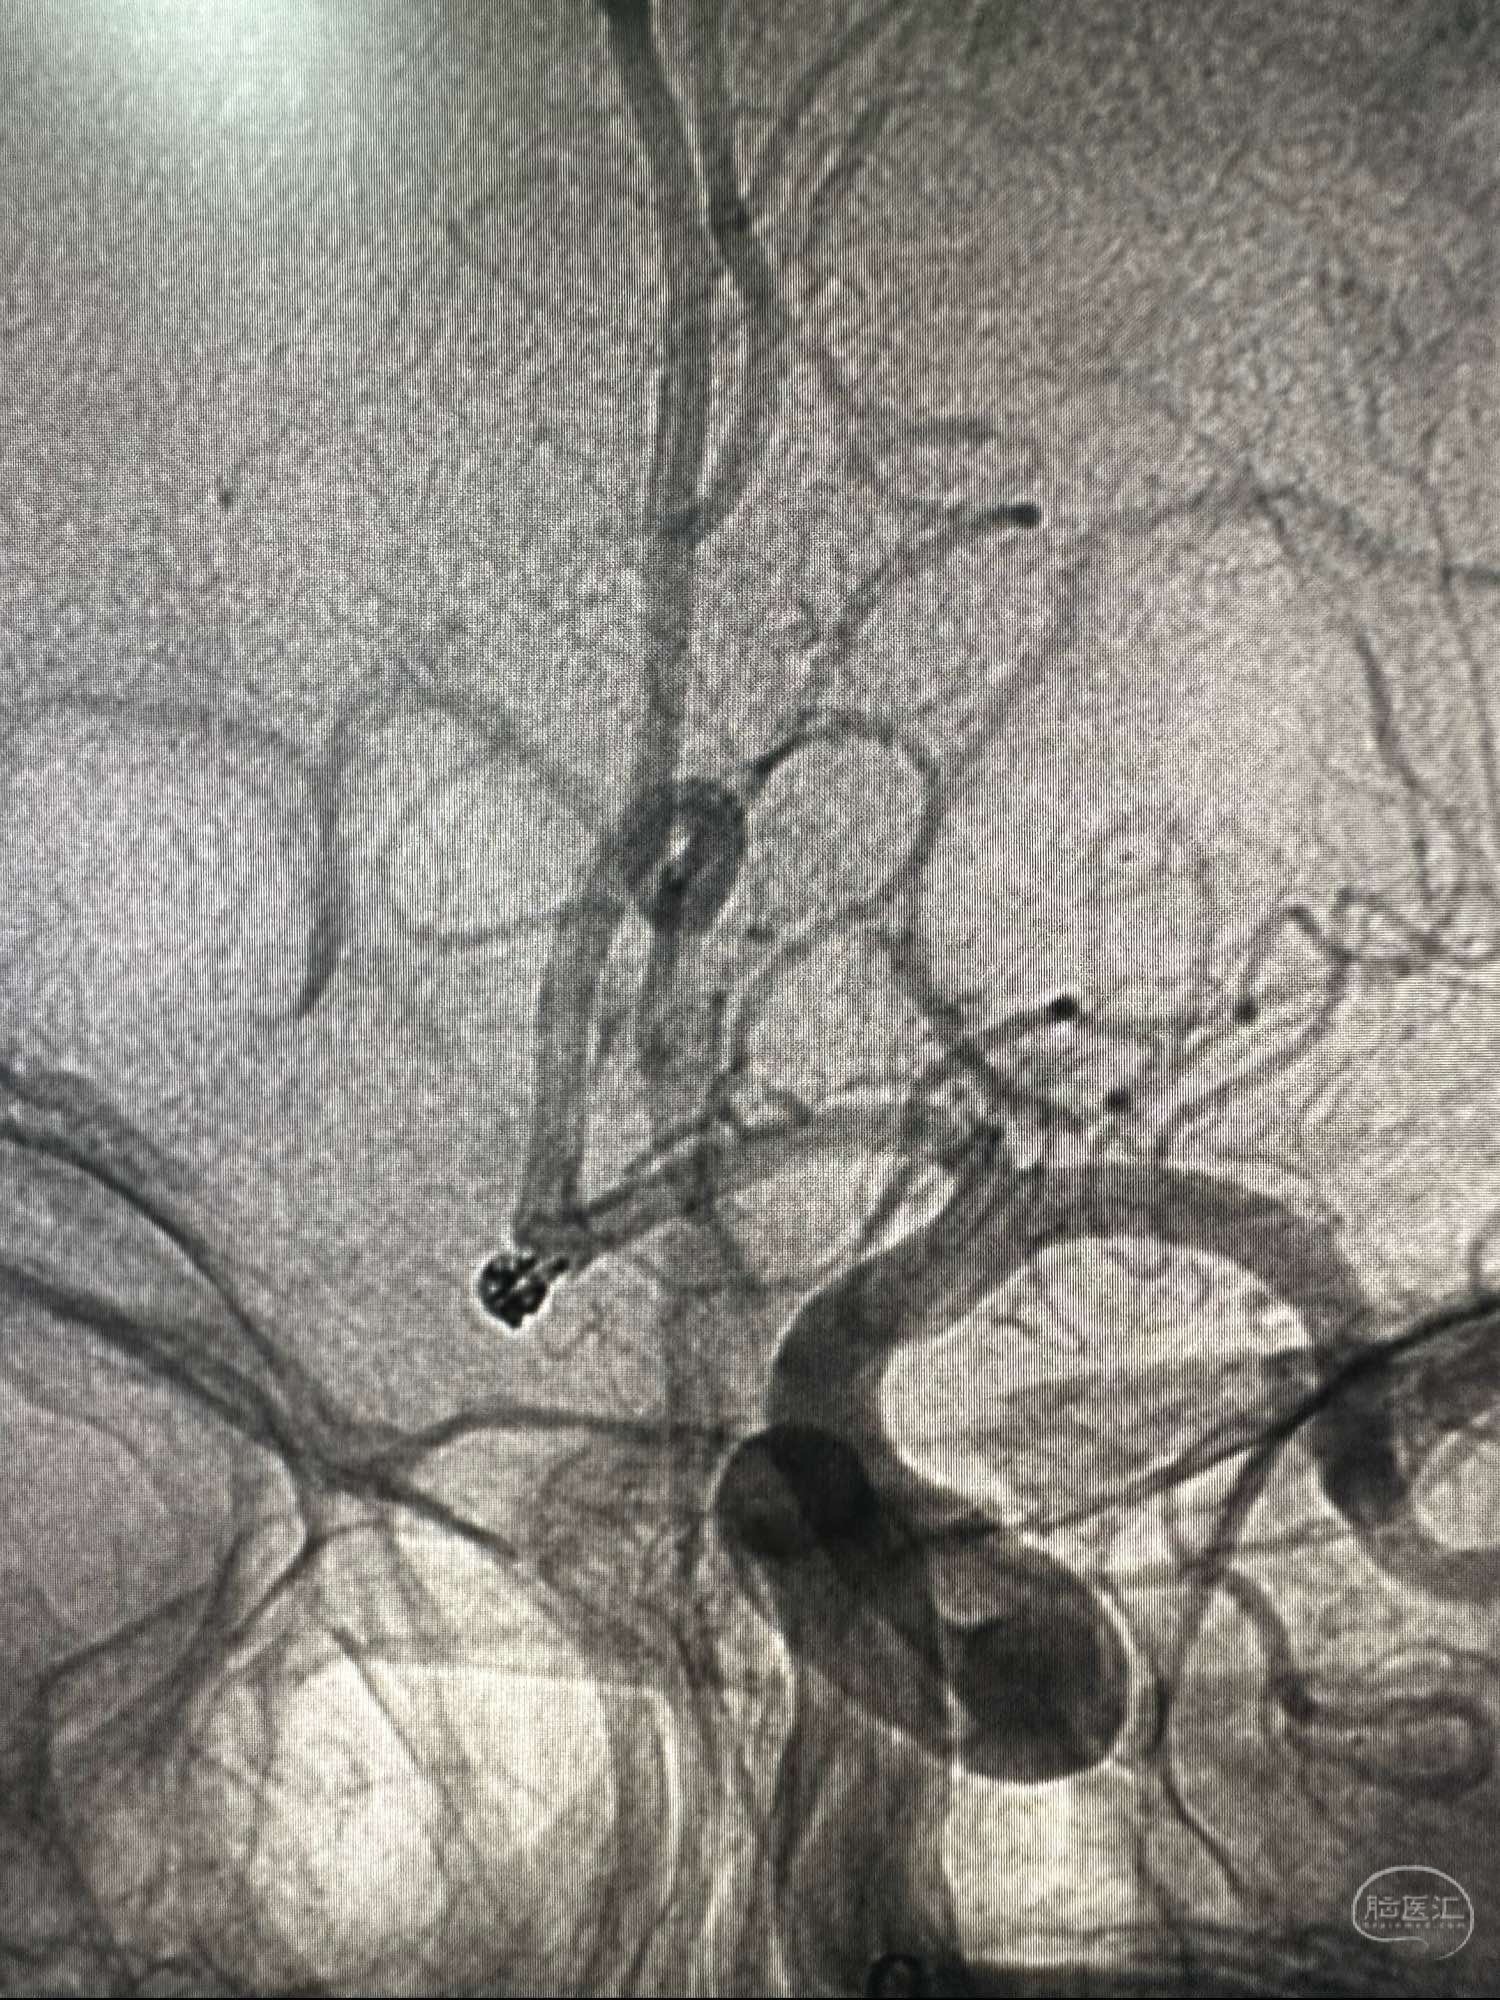

骨窗像